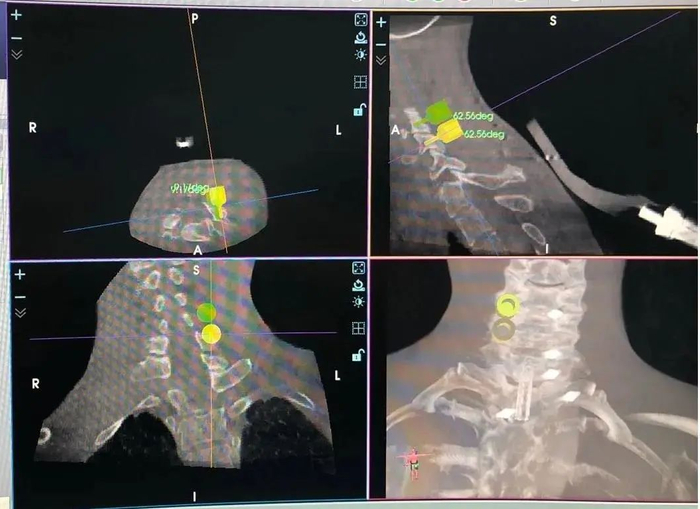

应用机器人进行颈椎后路侧块螺钉置钉规划

在骨科机器人手术关键技术及配套体系的创建方面,该团队完成了机器人辅助S2AI螺钉、微创颈椎后路侧块螺钉等特定部位的置钉、皮肤表面定位置针(颈、胸、腰)、置针防打滑操作、微创实心椎弓根钉置入、微创小关节融合等关键技术的创新及应用,并研发了相应的工具、装置及软件,对进一步推广骨科手术机器人的临床应用具有重要的意义。